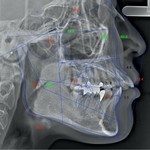

③各種レントゲン

詳細に関しましては下リンク先、当院のインビザライン特設ページにて解説しております。また、レントゲンに関しては本サイトの以前のコラムに詳しく記載しております。併せてそちらもご覧ください。

5⃣ 治療計画説明 について